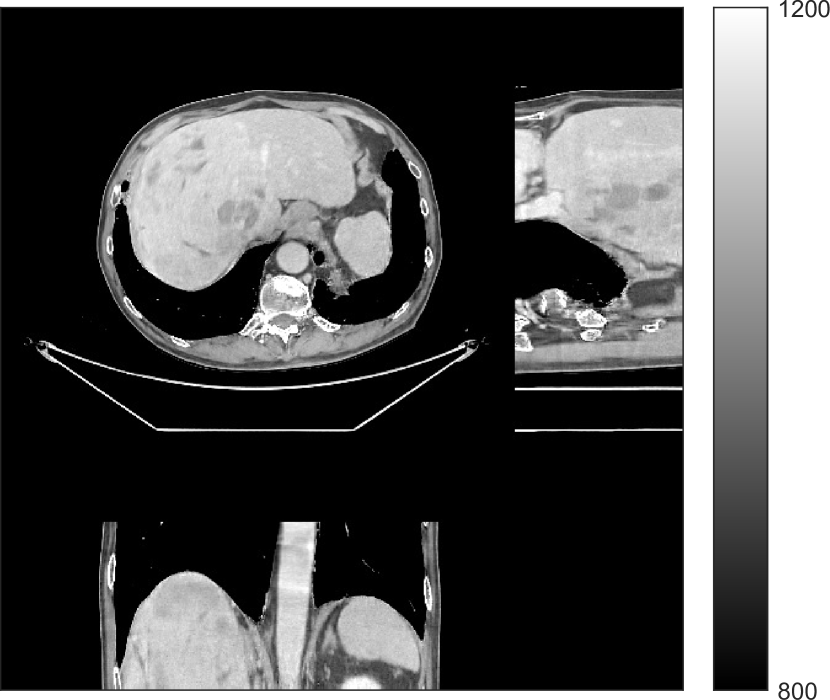

We used the pre-learned union of 15 square transforms from the XCAT phantom simulations to reconstruct the synthesized helical chest scan volume of size 420×420×222420420222{420\times 420\times 222} with Δx=Δy=1.1667subscriptΔ𝑥subscriptΔ𝑦1.1667\Delta_{x}=\Delta_{y}=1.1667 mm and Δz=0.625subscriptΔ𝑧0.625{\Delta_{z}=0.625} mm. The sinograms were of size 888×64×3611888643611888\times 64\times 3611. Since the clinical data is synthesized via the PWLS-ULTRA reconstruction, the noise model for this synthesized data is obscure, making it difficult to determine appropriate low-dose levels for such data. We tested the radiation dose of I0=1×104subscript𝐼01superscript104I_{0}=1\times 10^{4} with an electronic noise variance the same as the XCAT phantom simulation, i.e., σ2=25superscript𝜎225\sigma^{2}=25. The percentage of non-positive pre-log measurements for the synthesized clinical data in this case was around 0.14%percent0.140.14\%. Such non-positive values were replaced by 1×1051superscript1051\times 10^{-5} for PWLS-based methods. Fig. 8(a) shows the “true” clinical image that was reconstructed from real clinical regular-dose sinogram using the PWLS-ULTRA method.

Refer to caption

(a)

(b)

Figure 8: (a) “true” clinical image (HU), (b) the reconstruction (HU) of the synthesized data with PWLS-EP for I0=1×104subscript𝐼01superscript104I_{0}=1\times 10^{4} with βep=215subscript𝛽𝑒𝑝superscript215\beta_{ep}=2^{15}. The central axial, sagittal, and coronal slices of the volume are shown.

Similar to the XCAT phantom simulation, the initial image for both SPULTRA and PWLS-ULTRA was a reconstruction obtained using PWLS-EP. We set the regularizer parameter βepsubscript𝛽𝑒𝑝\beta_{ep} for PWLS-EP to 215superscript2152^{15} to generate a smoother (with less noise) initial image, which led to good visual image equality for the SPULTRA and PWLS-ULTRA reconstructions. Since the optimization problem for PWLS-EP is strictly convex, we simply initialized PWLS-EP with a zero image. Fig. 8(b) shows the PWLS-EP reconstructed image for I0=1×104subscript𝐼01superscript104I_{0}=1\times 10^{4}. We set the regularizer parameters for both PWLS-ULTRA and SPULTRA as γc=5×104subscript𝛾𝑐5superscript104\gamma_{c}=5\times 10^{-4}, and β=1.5×104𝛽1.5superscript104\beta=1.5\times 10^{4}.